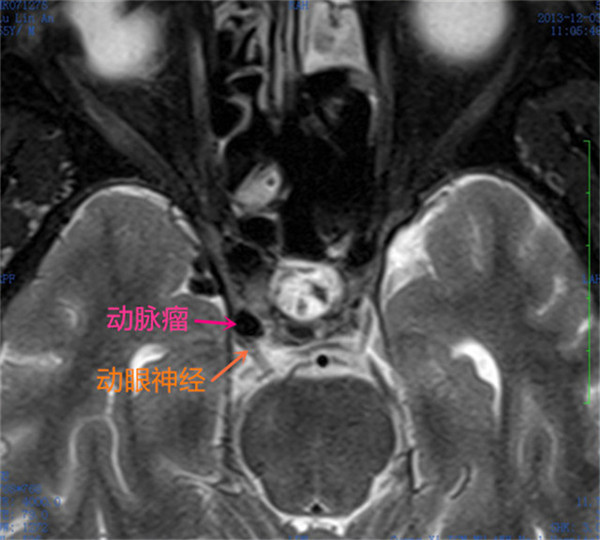

患者陆某某,男,58岁,因“右侧眼睑下垂、视力障碍半月”入院。诊断:1.右侧后交通动脉瘤,2.右侧动眼神经麻痹。入院后予以开颅动脉瘤夹闭手术并切除动脉瘤。术后2周,患者眼睑逐渐能睁开,眼球恢复活动,视力恢复。

术前MRI右侧动眼神经受压